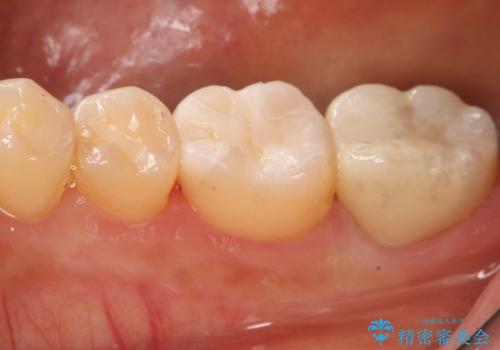

- 過去に他院で治療した部位が材料劣化を起こしていたため、セラミック治療を希望された患者様です。

切削量を考慮し、セラミックインレーを選択しました。

虫歯が深かったので、CRを詰めた上で形態を整えています。